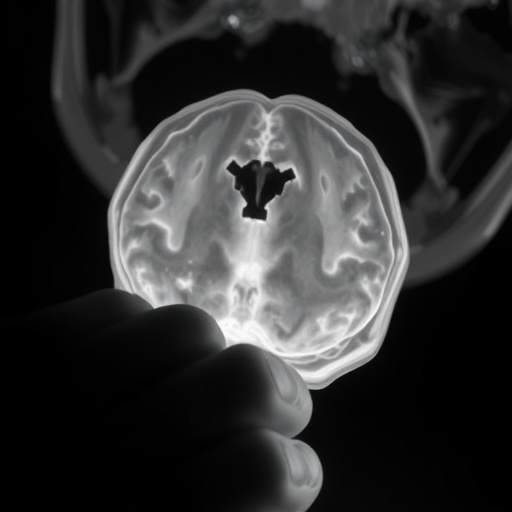

Neonatal encephalopathy broadly refers to a syndrome of disturbed neurological function in newborns, manifesting as altered consciousness, abnormal muscle tone, and seizures, frequently caused by hypoxic or ischemic events during the perinatal period. Despite its widespread clinical relevance, the terms ‘neonatal encephalopathy,’ ‘hypoxic-ischemic encephalopathy,’ and ‘perinatal asphyxia’ are often used interchangeably or inconsistently in research, which undermines the comparability of studies and the synthesis of evidence necessary for clinical advances. The comprehensive review scrutinizes how leading clinical trials define these entities, revealing a fragmented landscape riddled with variability and ambiguity.